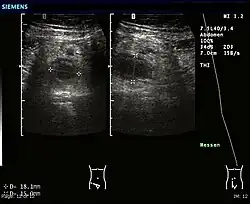

Abdominal ultrasonography, preferably with doppler sonography, is useful to detect appendicitis, especially in children. Ultrasound can show the free fluid collection in the right iliac fossa, along with a visible appendix with increased blood flow when using color Doppler, and noncompressibility of the appendix, as it is essentially a walled-off abscess. Other secondary sonographic signs of acute appendicitis include the presence of echogenic mesenteric fat surrounding the appendix and the acoustic shadowing of an appendicolith.[59] In some cases (approximately 5%),[60] ultrasonography of the iliac fossa does not reveal any abnormalities despite the presence of appendicitis. This false-negative finding is especially true of early appendicitis before the appendix has become significantly distended. Also, false-negative findings are more common in adults where larger amounts of fat and bowel gas make visualizing the appendix technically difficult. Despite these limitations, sonographic imaging with experienced hands can often distinguish between appendicitis and other diseases with similar symptoms. Some of these conditions include inflammation of lymph nodes near the appendix or pain originating from other pelvic organs such as the ovaries or Fallopian tubes. Ultrasounds may be either done by the radiology department or by the emergency physician.[61]

Ultrasound showing appendicitis and an appendicolith.[62]

Ultrasound of a normal appendix for comparison.

A normal appendix without and with compression. Absence of compressibility indicates appendicitis.[59]